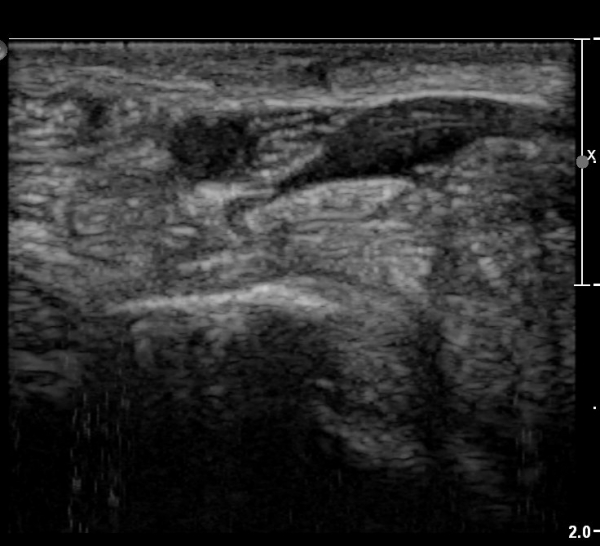

ÇÏŰ½ºÆ½(°íÁÖÆÄ) ŽÃËÀÚ¸¦·Î °üÂûµÈ ¸ð½À¿¡¼­ Á¤Áß½Å°æ ºÎºÐ ½Å°æ´Ù¹ßÀÇ Àú¿¡ÄÚ

º¯È­°¡ ¶Ñ·ÈÇÔ(»çÁø 6, 7).

Á¤Á߽Űæ Á¾´Ü¸é°Ë»ç¿¡¼­µµ ¼Õ¸ñ ¸»´ÜºÎ¿¡¼­ ¼ö±Ù°ü ±ÙÀ§ºÎ±îÁö À̾îÁø Àú¿¡ÄÚ

Á¾¾çÀÌ °üÂûµÊ(»çÁø 8, 9, 10, 11).